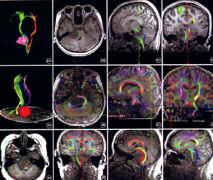

在磁共振成像脑,弥漫性脑干胶质瘤的特点是T1强度降低,异源T2增加。局灶性脑干神经胶质瘤的特征是T1为等信号至低信号至灰质,T2为高信号至灰质。 脑...

摘要:详细介绍脑干胶质瘤影像学、病理学、分子学分型 是什么决定着脑干胶质瘤手术、放化疗方案制定及预后评估,跟着专家咨询共识一文深入了解。...

脑干胶质瘤根据影像学表现和临床相关性可分为四种类型:弥漫性、局灶性、外生性和颈髓性。儿童脑干胶质瘤经常是急性发作的,具有病史短、预后差的...

儿童高级别脑干胶质瘤存活率,脑干胶质瘤不像其他部位的胶质瘤那样根据国际卫生组织对中枢神经系统肿瘤的分类进行分类,而是根据磁共振T1和T2加权成...